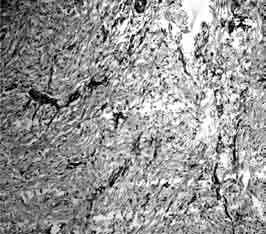

Язвенная болезнь относится к наиболее распространенным заболеваниям органов пищеварения. Врачи первого контакта (терапевты, общей врачебной практики) часто прибегают к стандартной диагностической и лечебной тактике при ведении данной категории пациентов. Однако определенная часть пациентов имеет сопутствующую патологию, нередко являющуюся фоном, отягощающим течение основного заболевания, и требует диффенцированного подхода к терапии с учетом фоновой патологии. Отмечены особенности морфологических изменений желудка у пациентов с дисплазией соединительной ткани, особенности моторно-эвакуаторной функции желудка и двенадцатиперстной кишки. По материалам собственных исследований сделаны выводы, позволяющие оптимизировать лечение язвенной болезни. В монографии показана целесообразность скрининга гастродуоденальных заболеваний при наличии внешних проявлений соединительнотканной дисплазии, в значительной мере это касается пациентов молодого возраста, имеющих симптомы диспепсии. Предложен комплекс мероприятий, направленных на коррекцию стандартизированного подхода к терапии язвенной болезни.